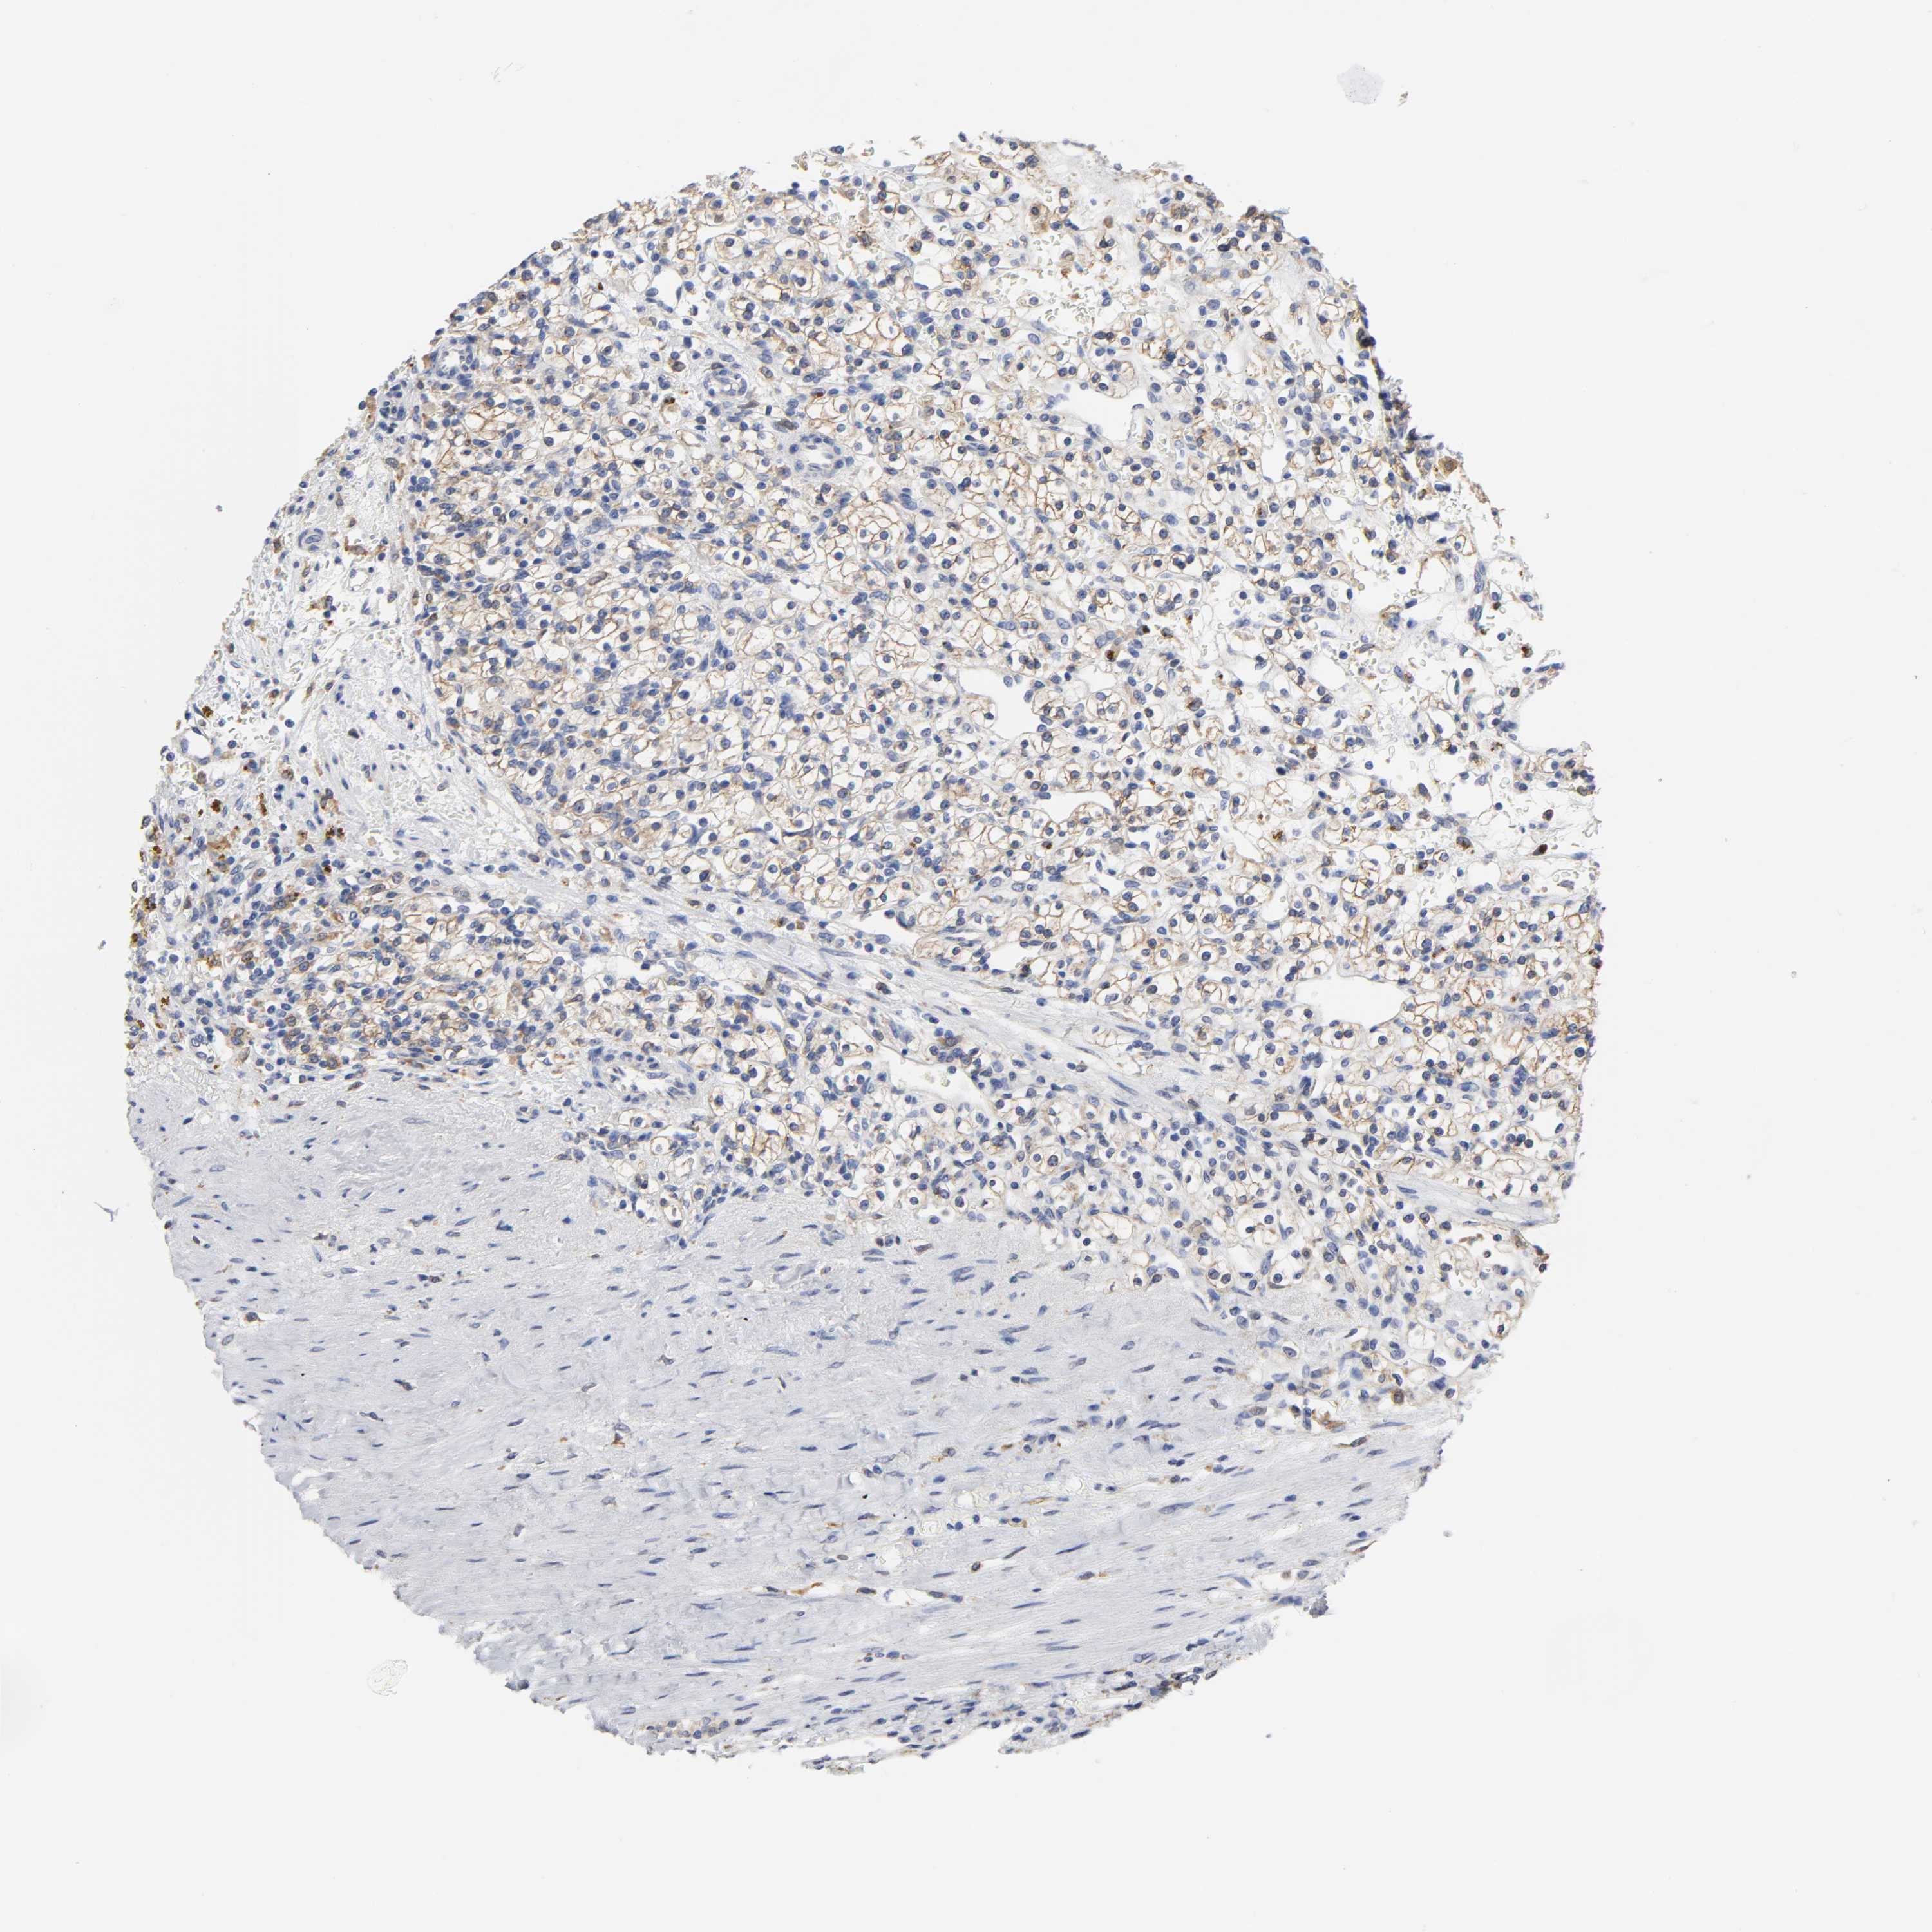

KIDNEY RENAL CLEAR CELL CARCINOMA (VALIDATION) - Interactive survival scatter ploti

The Survival Scatter plot shows the clinical status (i.e. dead or alive) for all individuals in the patient cohort, based on the same data that underlies the corresponding Kaplan-Meier plots. Patients that are alive at last time for follow-up are shown in blue and patients who have died during the study are shown in red.

HCK is not prognostic in Kidney Renal Clear Cell Carcinoma (validation)

Best expression cut offi

Based on the FPKM value of each gene, patients were classified into two groups and association between prognosis (survival) and gene expression (FPKM) was examined. The best expression cut-off refers the FPKM value that yields maximal difference with regard to survival between the two groups at the lowest log-rank P-value. Best expression cut-off was selected based on survival analysis .

When clicking on this number, the vertical dashed line indicating cut-off, the interactive survival plot, and the Kaplan-Meier curve will be adjusted to show results based on the best expression cut-off.

: 13.84

Average pTPM 28.2

Number of samples 100